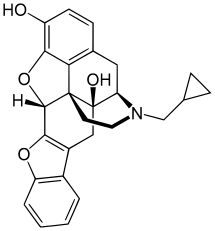

The pharmacodynamic response to an opioid depends upon the receptor to which it binds, its affinity for that receptor, and whether the opioid is an agonist or an antagonist. For example, the supraspinal analgesic properties of the opioid agonist morphine are mediated by activation of the μ1 receptor; respiratory depression and physical dependence by the μ2 receptor; and sedation and spinal analgesia by the κ receptor. Each group of opioid receptors elicits a distinct set of neurological responses, with the receptor subtypes (such as μ1 and μ2 for example) providing even more [measurably] specific responses. Unique to each opioid is its distinct binding affinity to the various classes of opioid receptors (e.g. the μ, κ, and δ opioid receptors are activated at different magnitudes according to the specific receptor binding affinities of the opioid). For example, the opiate alkaloid morphine exhibits high-affinity binding to the μ-opioid receptor, while ketazocine exhibits high affinity to ĸ receptors. It is this combinatorial mechanism that allows for such a wide class of opioids and molecular designs to exist, each with its own unique effect profile. Their individual molecular structure is also responsible for their different duration of action, whereby metabolic breakdown (such as N-dealkylation) is responsible for opioid metabolism.

Several semi-synthetic opioids were developed in Germany in the 1910s. The first, oxymorphone, was synthesized from thebaine, an opioid alkaloid in opium poppies, in 1914.[228] Next, Martin Freund and Edmund Speyer developed oxycodone, also from thebaine, at the University of Frankfurt in 1916.[229] In 1920, hydrocodone was prepared by Carl Mannich and Helene Löwenheim, deriving it from codeine. In 1924, hydromorphone was synthesized by adding hydrogen to morphine. Etorphine was synthesized in 1960, from the oripavine in opium poppy straw. Buprenorphine was discovered in 1972.[228]

- Buprenorphine

- Buprenorphine—partial agonist